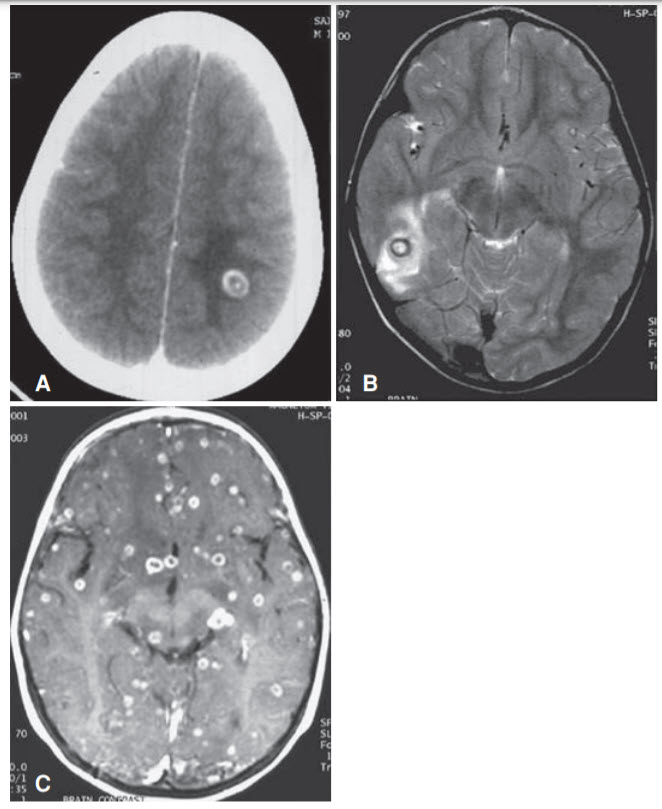

A 47-year-old man with no significant medical history presents to the Emergency Department after suffering his first seizure. He says that he has had headaches for the past week and has not felt himself. He lives with his family in California, and his mother recently moved in with him after immigrating to the United States from El Salvador. He is afebrile with normal vital signs, and a brief screening physical examination is normal. He is currently alert and oriented to person, place, and time. An MRI of the brain is shown in Figure below.

Albendazole, dexamethasone, and levetiracetam. The brain imaging above shows a scolex (first two images) and many nonenhancing cysts with surrounding edema (third image). A scolex within the cyst cavity is pathognomonic for neurocysticercosis, one of the manifestations of infection by the pork tapeworm Taenia solium. Neurocysticercosis is the most common cause of seizure in Central America, and this patient’s mother recently immigrated from El Salvador. Neurocysticercosis is not caused by ingesting infected pork; those who eat infected pork become carriers of cysticercosis, but do not develop disseminated cysticercosis (e.g., neurocysticercosis). It is only by ingesting eggs shed in the carrier’s feces (e.g., fecal contamination of food) that one develops neurocysticercosis, since it is the embryos that hatch from the eggs that disseminate hematogenously. Treatment is with an antiparasitic agent (e.g., albendazole or praziquantel), and a corticosteroid should be added to reduce inflammation in response to the dying pathogens. (B) Because the patient presented with a seizure, an antiepileptic medication should be started in addition to an antiparasitic medication and a corticosteroid. (Of note, antiparasitic medications are not necessary if there are calcified cysts with no viable parasites.)

(C) Pyrimethamine-sulfadiazine is the treatment for toxoplasmosis, which presents with ring-enhancing lesions on brain imaging. (D, E) Vancomycin and amphotericin B are typically used for MRSA and serious fungal infections, respectively, and are not used for neurocysticercosis.